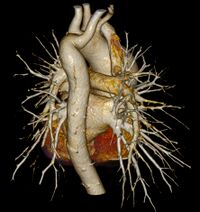

Lusory artery is aberrant branch of a. subclavie. It withdraws as the last branch of the aortic arch behind the left subclavian artery, or from the descending part of the aorta. It passes through the rear mediastinum usually behind osesophagus and because of the pressure caused by the oesophagus it can cause dysfagic problems (ie. dysphagia lusoria), it cen exceptionally pass between oesophagus and trachea and compress the respiratory tract and cause prolonged cough of infants. It can also press on n. laryngeus recurrens sinister and lead to Ortner's syndroms. Aberrant branch can also be associated with the so-called Kommerell's diverticulum.